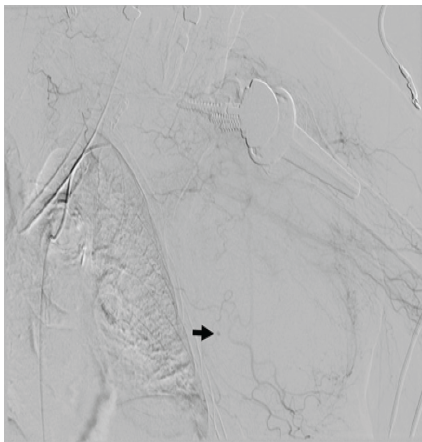

Hemoglobin also dropped acutely from 7.5 g/dL to 4.8 g/dL. Warfarin reversal was initiated immediately with two units of fresh frozen plasma and intravenous vitamin K, followed by 2,000 units of prothrombin complex concentrate to more expeditiously reverse anticoagulation without causing hypervolemia. Two units of packed red blood cells were administered, increasing her hemoglobin to 8.4 g/dL and resolving the hemodynamic instability. Computed tomography (CT) of angiography of the left upper extremity was obtained and revealed a large pectoral hematoma measuring 16.0 × 9.6 × 17.5 cm with active contrast extravasation from the lateral pectoral artery, a branch of the second segment of the axillary artery (Fig. 4). INR decreased from 3.8 to 1 by the next day.

Figure 4: Angiogram demonstrating contrast extravasation from a branch of the lateral pectoral artery in the soft tissues of the left chest wall (arrow).